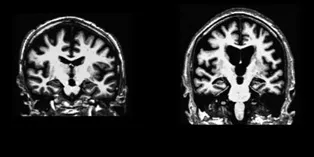

Duke researchers have identified the ways in which aging brains deteriorate when they have shortened sleep. Brain function was evaluated by in-person and MRI assessments every two years following 66 generally healthy Chinese adults, starting at the age of 55. For every hour of lost sleep, the ventricles expanded and cognitive skills declined, compared to those who maintained a healthy sleep duration. The sleep-deprived brains looked more like the brain on the right in the picture: the brain with the large black (no-brain) spaces, now filled with fluid where there used to be brain, what is called “ventricular enlargement,” which really amounts to loss of brain tissue.

The pictures, by the way, should be labeled “Normal” on the left and “Alzheimer’s” on the right.